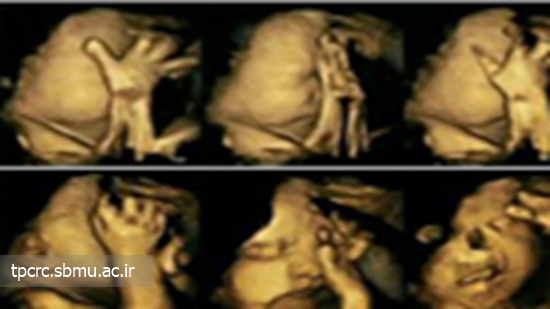

مطالعهای جدید با منتشر کردن تصاویری 4 بعدی سونوگرافی تاثیرات سیگار کشیدن را در دوران بارداری نشان میدهد. این حقیقت که سیگار کشیدن مادر در دوران بارداری یا قبل از آن چه تاثیرات منفی بر جنین میگذارد بر کسی پوشیده نیست اما برخی افراد این موضوع را جدی نمیگیرند.

این تصاویر که طی سونوگرافی از جنین مادرانی گرفته شده است که سیگار میکشیدند به خوبی نشان میدهد سیگار با جنین چه میکند.

گفته میشود سیگار کشیدن مادر باعث میشد دهان جنین بیشتر تکان بخورد تا حدی که حرکت کند و ممکن است لبشکری شود یا بیشتر دست خود را به سمت صورتش بیاورد و آن را لمس کند.

محققان علت این حرکت غیرعادی جنین را اختلال در عملکرد سیستم عصبی مرکزی او میدانند. این سیستم حرکات و واکنشهای فیزیکی کلی بدن جنین به خصوص حرکات صورت را کنترل میکند.

سیگار کشیدن مادر در دوران بارداری عملکرد سیستم عصبی جنین را با مشکلاتی روبه رو میکند که در این تصاویر بهخوبی قابل مشاهده است. یافتههای مطالعاتی که وضعیت جنین را در زنان باردار سالم و سیگاری بررسی کرد نشان داد نیکوتین چند برابر بیشتر از عواملی همچون فشار روحی و افسردگی میتواند سلامتی جنین را تحت تاثیر قرار دهد.

این تصاویر از جنینهایی گرفته شده است که مادرانشان در دوران بارداری دخانیات استعمال میکردند و یا در معرض دورد سیگار بوده اند در بین هفتههای 24 و 36 بارداری گرفته شده است.